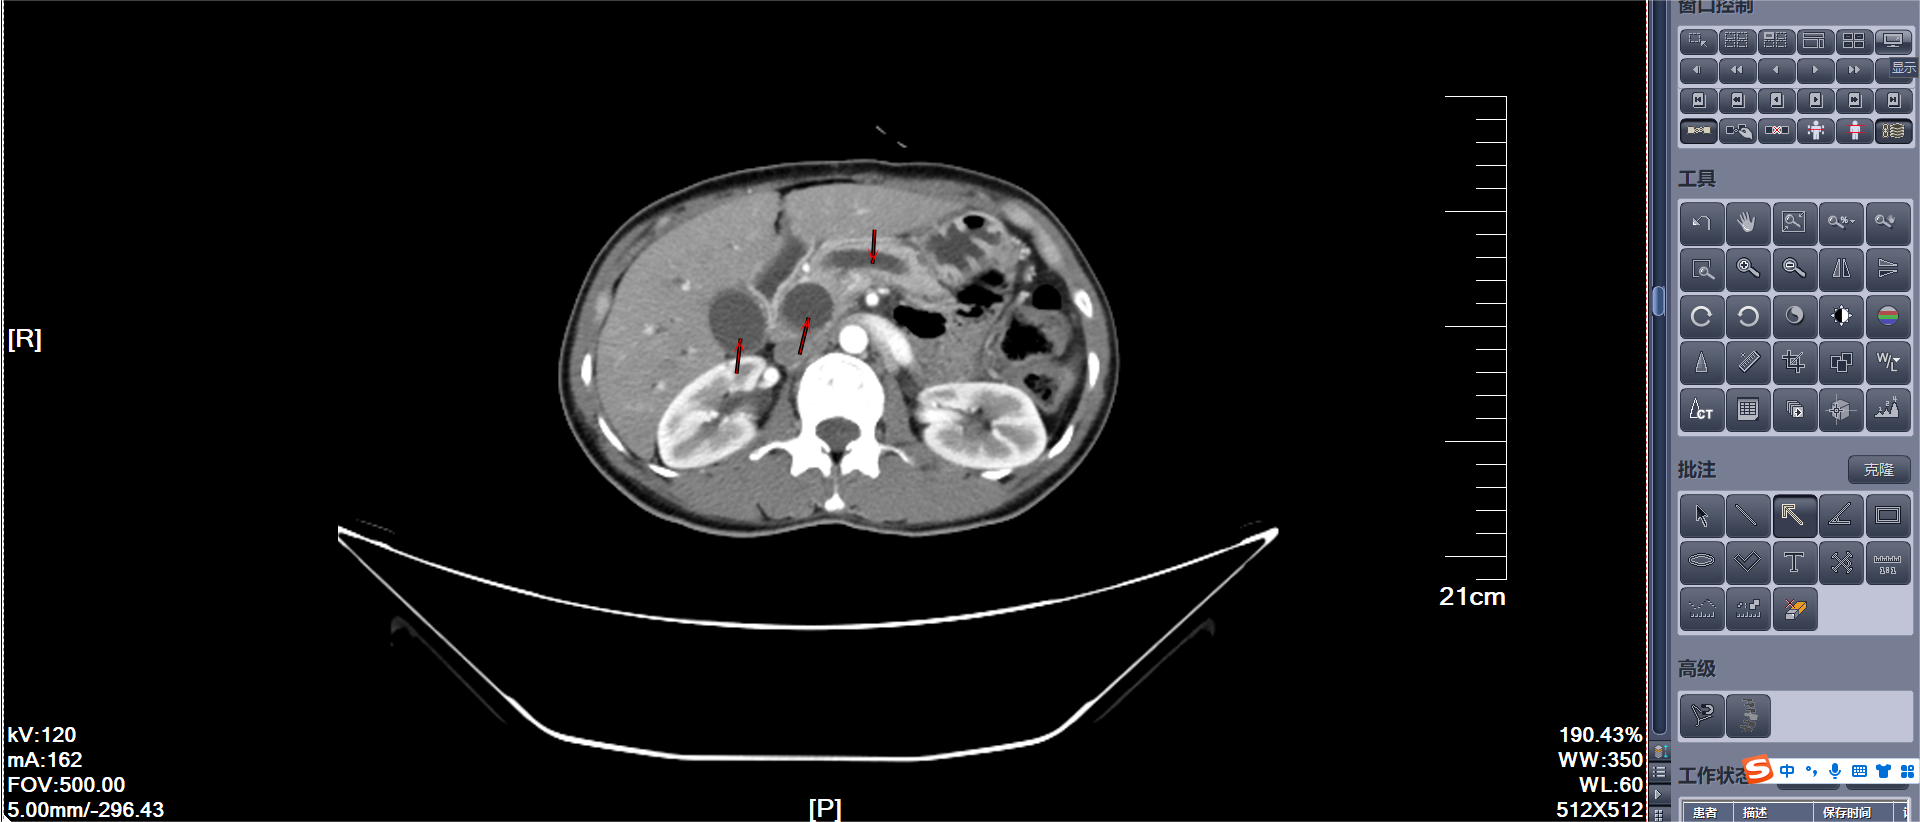

手术大体标本:十二指肠壶腹部肿瘤(红色圈)

患者于术后2周出院,出院时患者肝功能基本恢复正常,胆红素水平接近正常,黄疸、皮肤瘙痒等症状基本消失。术后病理示:十二指肠壶腹部腺癌,中分化,胰胆管型,浸润至十二指肠深肌层,未见脉管癌栓及神经侵犯。